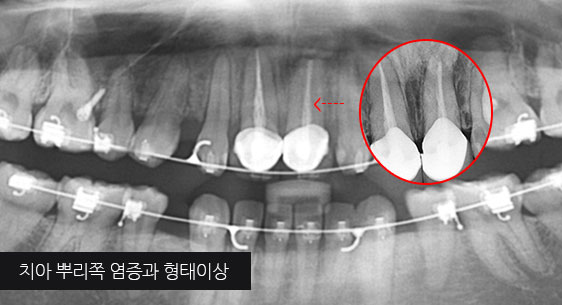

신경관이 막혀 있는 경우 재신경치료로 낫지 않는 경우, 포스트가 있어 재 신경 치료를 할 수 없는 경우, 치아 뿌리 까지 염증이 심하지만 이러한 염증을

제거 할 수 없는 경우, 고운미소 치과에서는 치조골 주위 염증조직을 제거하는 치근단절제술을 시행합니다.

기존 신경치료는 양호한 상태이나 치근부위에 염증과 치조골 소실이 진행 중

치아 뿌리 쪽 잇몸을 절개하고 치조골 부위의 염증조직을 제거. (난이도 중)